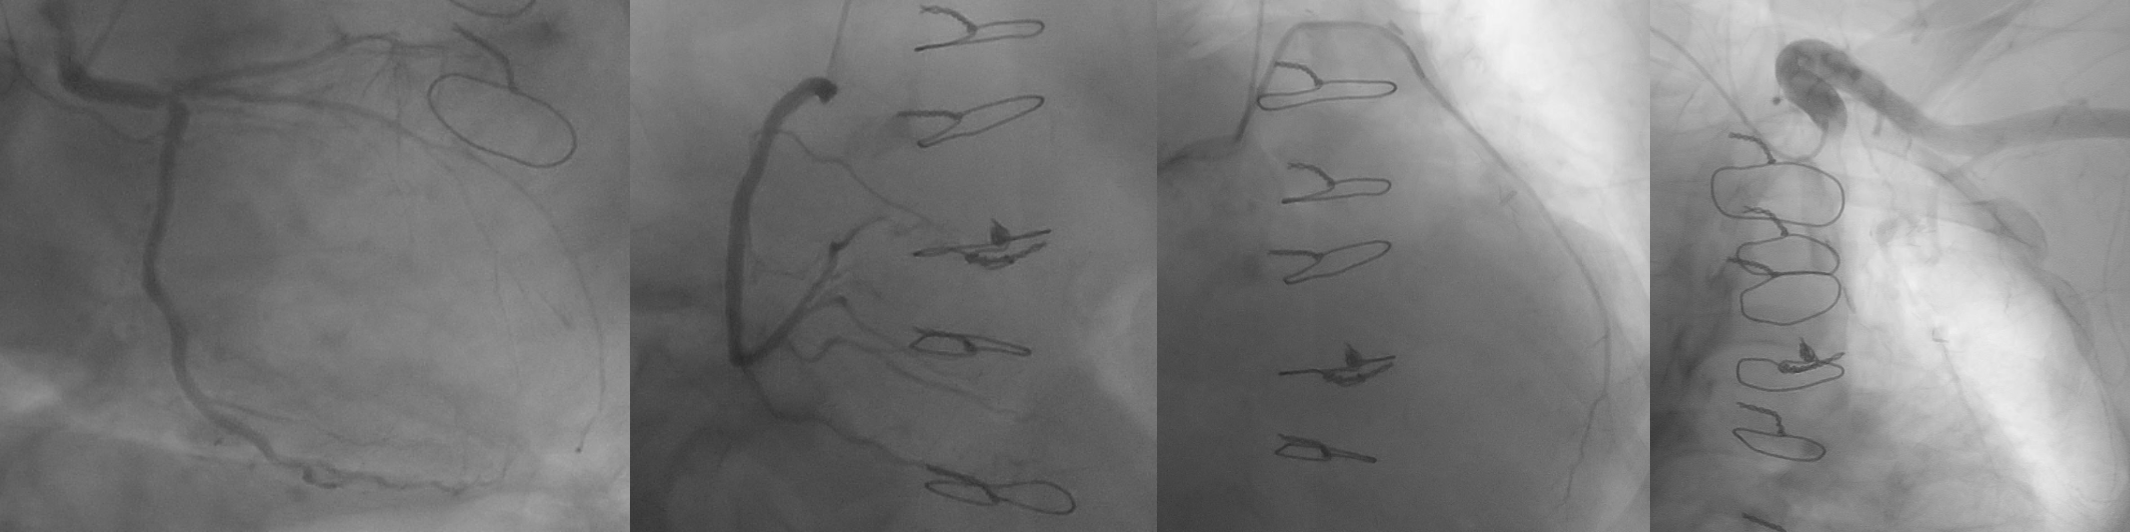

Her echo showed LVEF 41%, severe bicuspid aortic stenosis with fusion RCC/NCC, Mean/Max 37/65mmHg, Vmax4.02m/s, AVA 0.8cm2 with mild to moderate aortic regurgitation. Her coronary angiogram and graft study showed patent LIMA-LAD, radial-diagonal grafts, eccentric distal LM disease extending into ostial LAD and non obstructive LCx and RCA disease. The left subclavian artery appeared severely tortuous as well.

Relevant Catheterization Findings

CT-TAVI confirmed Type 1B (RCC-NCC fusion) bicuspid aortic stenosis with severe raphe calcification. Aortic annulus area 486mm2, Area derived diameter 24.9mm. Other CT parameters are as attached. Both iliofemoral arteries diameter and morphology is satisfactory for transfemoral access. However, there is extreme tortuosity of her descending aorta with almost complete S shape but no significant disease or calcification throughout.

She was turned down for surgical AVR (STS 6.2%, EuroScoreII 8.0%, resternotomy, high BMI, short stature, kyphoscoliosis, COPD and breast cancer history) during Heart Team discussion. For TAVI risk, she is a young lady with almost type 0 bicuspid aortic stenosis and severely calcified raphe, tortuous aorta and left subclavian artery. We had discussed multiple strategy and decided for left transfemoral TAVI using Evolut FX 29mm. After 18mm balloon valve predilation, we successfully delivered THV to aortic root with 1 Lunderquist wire on first attempt. After satisfactory positioning, the THV had prolapsed during initial deployment. We were unable to recapture the THV nose cone tip for repositioning despite multiple maneuvers. We managed to realign the nose cone tip and fully recapture the THV by retracting to straighter part of descending aorta.This time, we had to use 2 Lunderquist wire to redeliver THV across the aortic arch. This maneuver was repeated 3 times as the THV would not remain in place due to the complex calcified nature of bicuspid valve and severe aorta tortuosity. We decided to switch to plan B using a new THV platform - Sapien 3 Ultra Resilia 23mm+1. We exchanged to E-Sheath 14Fr and successfully deliver new THV around the curves using 2 Lunderquist buddy wire. After satisfactory positioning, we successfully deployed the new THV under rapid pacing with excellent angiographic and echocardiographic results. The patient was well and discharged at day 3 post TAVI.